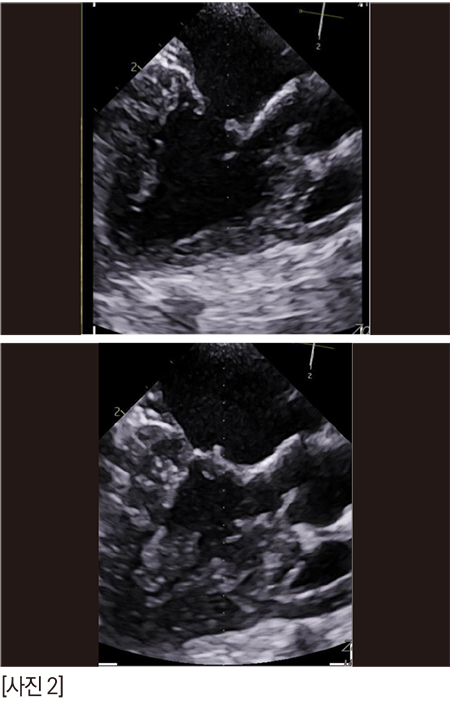

zone 2의 스틸컷이다. 어때 보이는가? 잘 닫히고 괜찮은가?

anterior leaflet의 끝단이 flail 되고 있다. 늘상 만나는 심각한 수준의 아이들 보다는 좀 낫긴 한데, 퇴행성 변화로 판막의 끝단이 너덜거리고, anterior leaflet의 건삭은 조금씩 닳아서 끊어지고 있나보다. 끝단이 좌심방을 향해 있다.

anterior의 zone 2-3과 posterior의 zone 2가 좀 뒤집어지고 있다. 이것은 건삭의 일부가 끊어져 너덜거리는 것으로 예측한다. 2D에서는 역류가 심해 보이지 않았지만 3D에서는 꽤 심해 보인다.